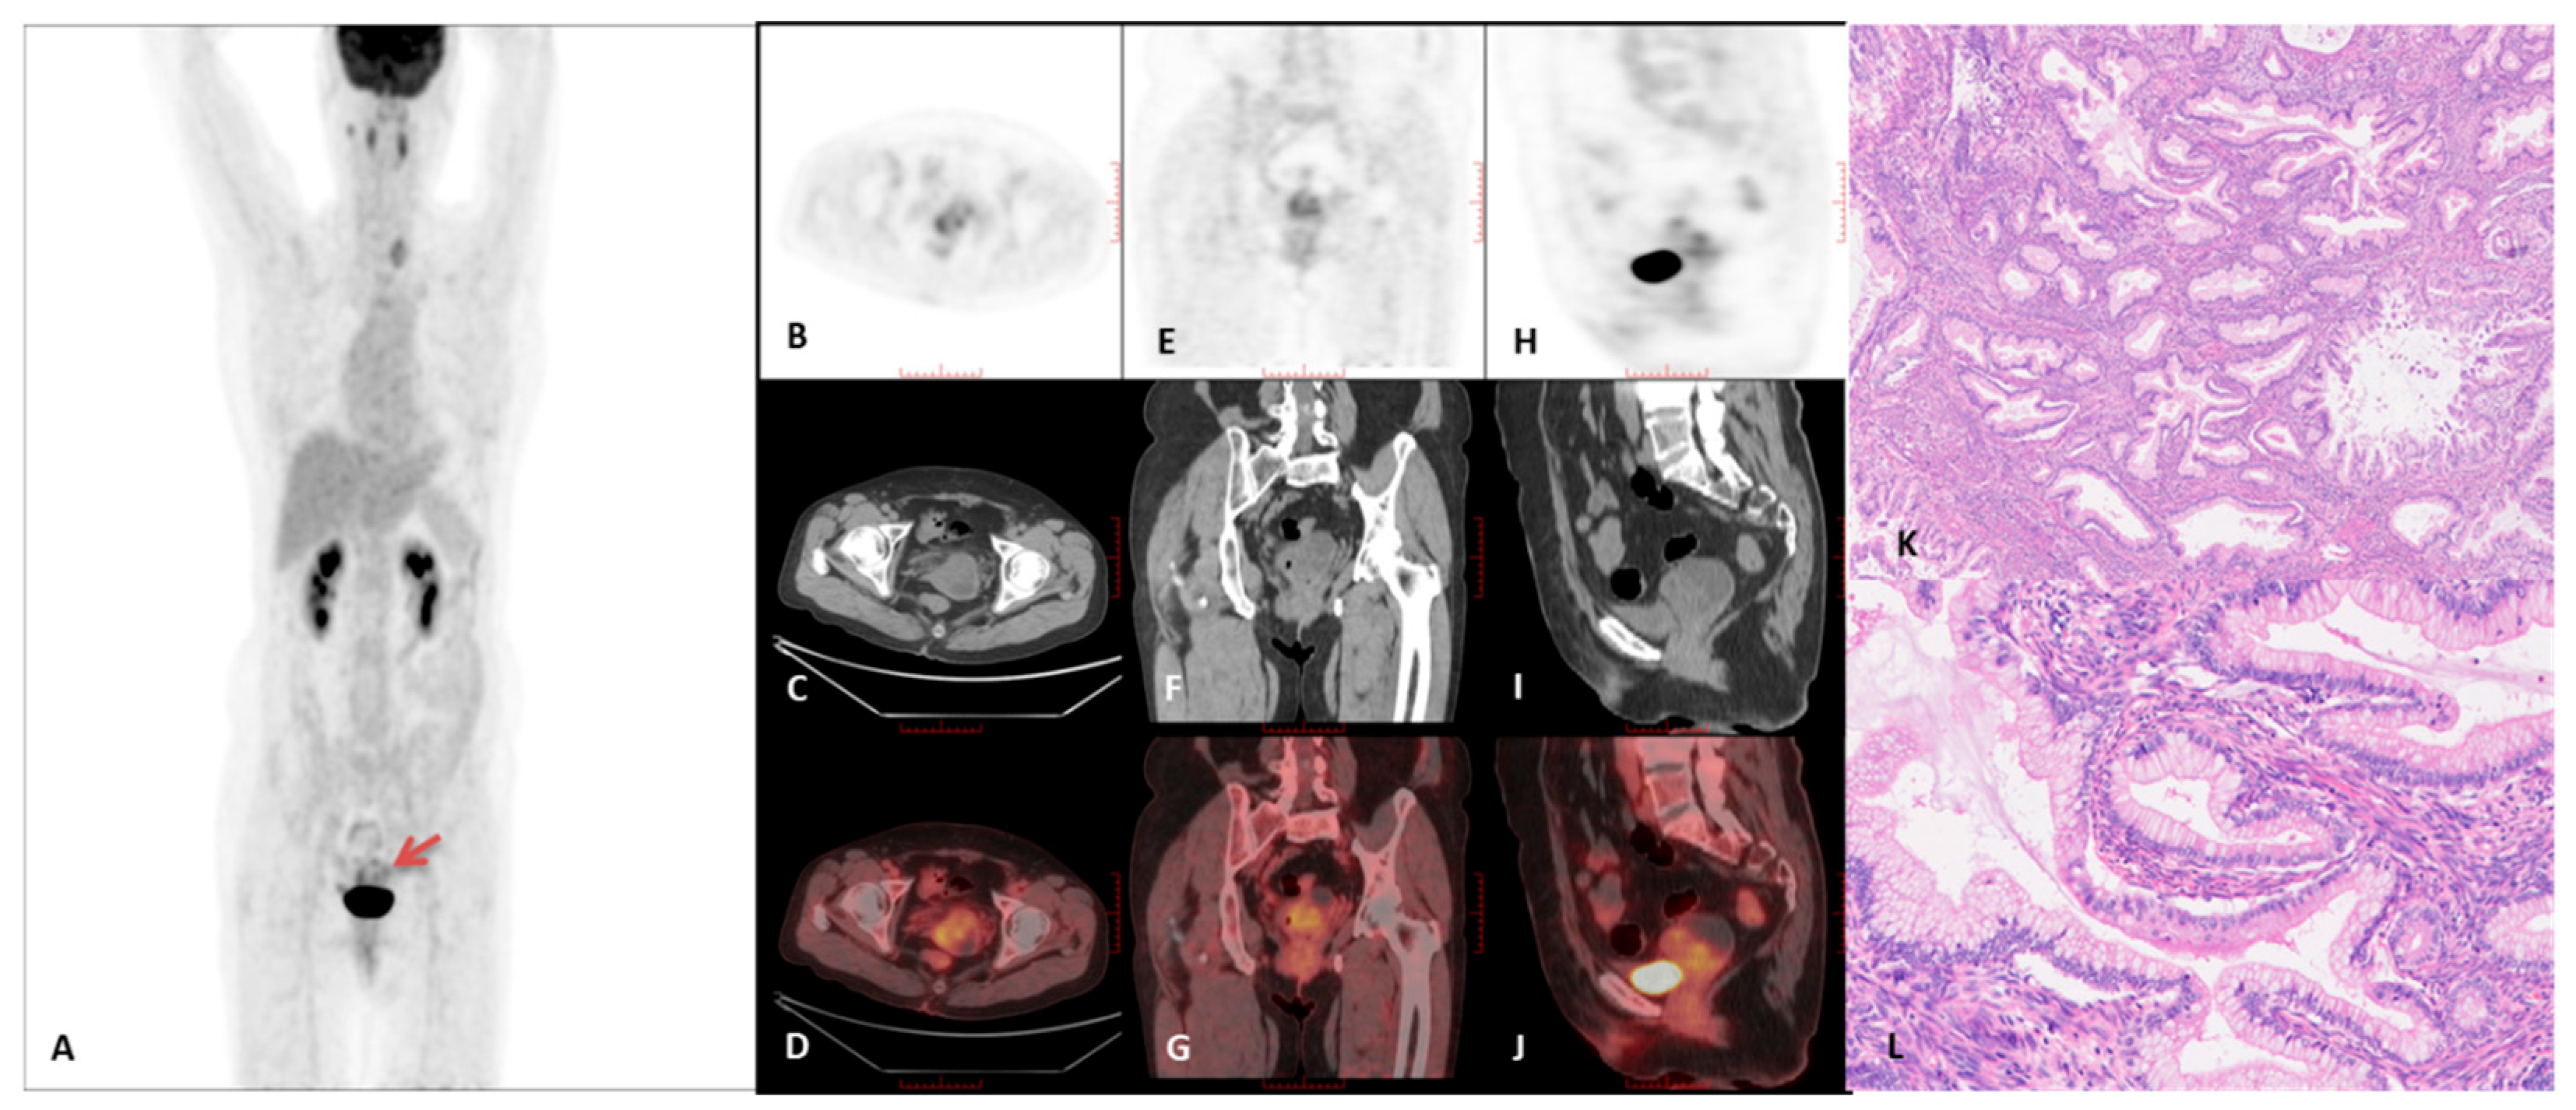

3.2. PET/CT Imaging Characteristics

| Case # | FIGO 2018 | Tumor Diameter Mean Value (cm) | Macrocysts | Tumor Growth Pattern | Intrauterine Fluid | SUVmax | T/L SUVmax |

|---|---|---|---|---|---|---|---|

| 1 | IVB | 2.9 | Present | Diffuse | Present | 3.0 | 1.0 |

| 2 | IVA | 2.4 | Present | Diffuse | Present | 2.8 | 1.1 |

| 3 | IB | 3.7 | Present | Diffuse | Present | 2.6 | 0.8 |

| 4 | IVB | 6.5 | Present | Diffuse | Present | 9.3 | 3.9 |

| 5 | IVB | 3.3 | Present | Mass | Present | 9.7 | 2.7 |

| 6 | IIIC | 4.8 | Present | Diffuse | Present | 11.6 | 3.1 |

| 7 | IIA | 4.6 | Present | Diffuse | Present | 6.8 | 1.7 |

| 8 | IVB | 2.9 | Present | Diffuse | Present | 12.6 | 3.8 |

| 9 | IVB | 5.2 | Microcysts | Diffuse | Present | 6.2 | 1.9 |

| 10 | IVB | 5.9 | Present | Diffuse | Absent | 13.3 | 6.0 |

| 11 | IVB | 6.8 | Present | Diffuse | Present | 7.7 | 3.1 |

| 12 | IVB | 3.7 | Present | Diffuse | Present | 4.5 | 1.2 |